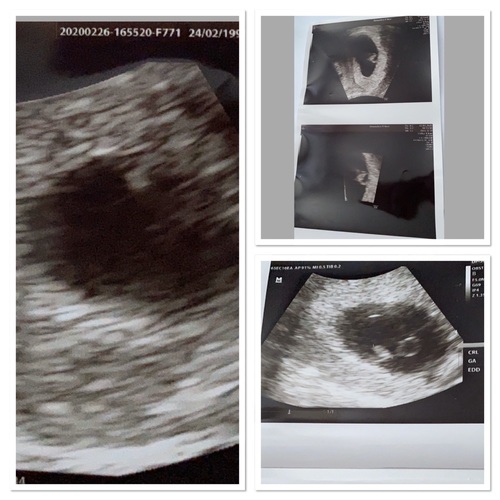

Dit zijn mijn foto’s van 26 feb 2 maart en 13 maart

Die van 13 maart is al wel echt heel duidelijk! Hoe ver was je daar? En ik vind die van 2 maart vergelijkbaar met die van mij.. (lijkt op de foto miss anders maar denk dat ik een slechte foto heb meegekregen op bewegend beeld vond ik het er anders uit zien) hoe ver was je daar?

Volgens de verloskundige was ik op me echo van gister pas 6+2. terwijl het ziekenhuis op 2 maart tegen mij zegt dat ik daar al 6+2 ben. Dan komen we dus op het feit dat het vruchtje gewoon niet gegroeid is dat het dus de verkeerde kant op gaat of het ziekenhuis heeft een verkeerde berekening gemaakt.🤷🏼♀️(omdat we inmiddels 2 weken verder zijn hoorde ik dan nu 7/8 weken te zijn...) de eerste echo foto weten we niet hoever dat geweest zal zijn!